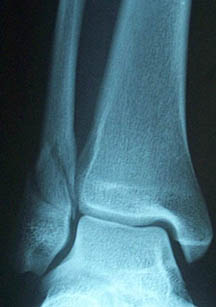

I got taken to a local hospital in Wairoa then discharged later that day. I wanted to be fixed up closer to home. I was in Waikato hospital for four nights and had surgery on my ankle. They also found that I had a broken tibia.